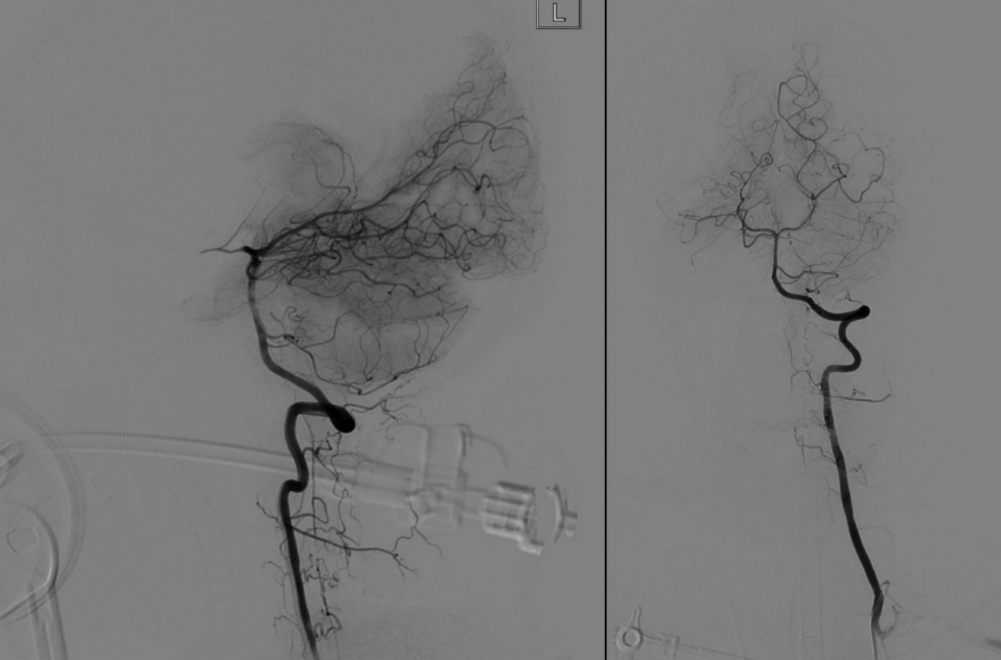

复合手术室行术中脊髓造影明确畸形血管团位置

手术当天,医疗团队首先在复合手术室内为患者进行了脊髓血管造影。在神经外科张昊副主任医师和邓敏峰博士的精准操作下,术中脊髓造影成功明确了畸形血管团的“位置”。

畸形血管团切除后立即脊髓造影明确完整切除

切除完成后,再次进行了造影复核,确认畸形血管团已被完全切除,手术取得了圆满成功。